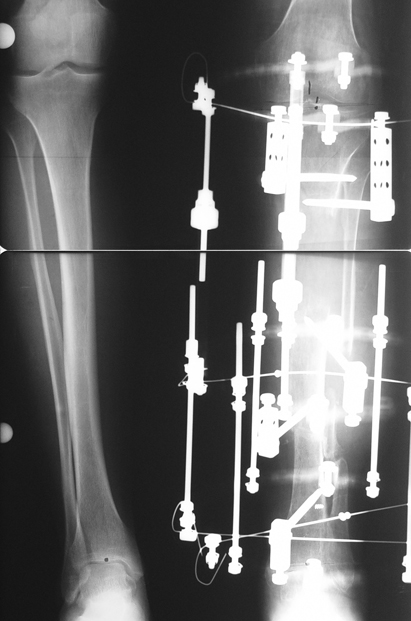

The duration of external fixation (external fixation index) depends on the amount of distraction required, and the extremity is prone to complications during this period. After the distraction phase is completed, the external fixator remains in place during the consolidation phase, which lasts twice as long as the distraction phase; but this period is hardly tolerated. If the external fixator is removed before sufficient consolidation is achieved, fractures, deformity and shortness will be the result. In our department, ‘lenghthening over nail’ method is used in order to decrease the external fixation index and increase patient comfort and activity level. In this method, the intramedullary nail is statically locked after the completion of the distraction phase, and external fixator is removed. The extremity is stabilized by the intramedullary nail during consolidation phase. In this way, complications due to long external fixation index or early removal of the external fixator are avoided.

Case 3